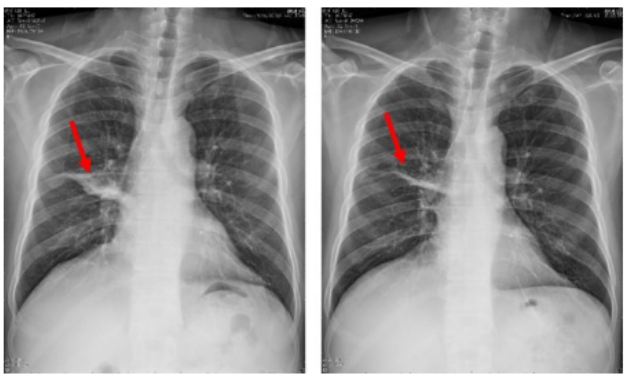

支气管镜在肺真菌病治疗中的应用主要有:①通畅气道:清除气道潴留物,解除机械阻塞。②冲洗引流:脓腔冲洗引流;液性病灶穿刺引流;炎症部位支气管冲洗;导管冲洗;穿刺引流。③局部用药:支气管冲洗、留置导管注药、药物缓释系统置入。病例:一名45岁男性因咳嗽、咳黄痰、呼吸困难持续5个月入院,患者胸部CT提示肿块引起的阻塞性肺不张(图3),但初步病理活检并未明确支持肿瘤诊断。这种不确定性可能与浅表取样有关,但不能完全排除肿瘤病变,使用硬质支气管镜检查缓解气道阻塞。术中见气道内白色肿块,该肿块松散地附着在支气管壁上(图4),镊子取出肿块时出血极少。肿块的组织学检查显示慢性化脓性炎症和肉芽肿形成、提示新型隐球菌感染。通过宏基因组二代测序证实了BALF中新生梭菌的存在。同时,血清隐球菌荚膜抗原检测结果呈阳性,氟康唑抗感染后痊愈。注:A:右主支气管和右中支气管有肿块,右下叶不张;B:右主支气管肿块消失,肺复张;C:右主支气管肿块完全消失和完全肺复张。图源:Medicine (Baltimore), 2024, 103(12):e37455.注:A:硬质支气管镜检查前软性支气管镜检查,显示右侧主支气管有肿块,导致闭塞;B:硬质支气管镜检查3天后软性支气管镜检查,证明成功从右侧主支气管中切除肿块。图源:Medicine (Baltimore), 2024, 103(12):e37455.隐球菌病胸部CT大部分表现为结节影,部分可有实变和坏死。支气管内隐球菌病导致的严重气道阻塞病例罕见,我们认为选择早期呼吸干预是一种理性的选择。首先,近一半的阻塞性支气管内隐球菌病患者对抗真菌药物反应不佳。其次,长期肺不张对肺复张构成挑战,可能导致永久性肺塌陷和肺功能受损,甚至最终导致肺实质感染和纤维化。软性支气管镜检查有助于区分内在性梗阻和外在压迫性,而硬质支气管镜检查可以更好地了解内在性梗阻性病变的性质,并提供一种气管内治疗手段。毛霉菌极易堵塞局部血管和支气管,病灶药物浓度低,单纯的全身药物治疗效果并不理想。近年来的研究发现两性霉素B局部给药,在抗真菌治疗方面会起到一定的辅助作用,包括雾化吸入、鞘内注射等,经支气管镜应用两性霉素B局部灌注对肺毛霉病可取得良好的效果。对于支气管被毛霉的菌丝体阻塞的患者,采用积极的介入治疗也可取得一定的效果,但应小心谨慎,防止出现大出血。各种介入治疗方法,包括两性霉素B局部灌注、冷冻治疗等,获得了不错的疗效。肺毛霉病的介入治疗必须具备全身麻醉、气管插管、预置球囊及有经验的呼吸内镜介入团队等。冷冻治疗建议在全麻气管插管方式下实施,出血风险高的患者还需要预置止血球囊。研究报道,10例肺毛霉病介入治疗患者均临床治愈,死亡0例。10例患者中应用冷冻探头冻取病灶8例,活检钳钳除病灶7例,套器套治疗2例,异物钳钳取病灶2例。介入和治疗经支气管镜直接局部灌注同步进行,1次/周,共1~6次。冷冻治疗的过程中3例患者预置球囊防止支气管内出血。10例患者中4级出血1例,3级出血2例,2级出血4例,3例患者无出血。支气管内出血均在5~10 min停止,术后少量痰中带血3~4天,术后气胸0例。牟向东教授团队在应用全身+局部治疗肺毛霉病的同时联合气管镜下介入技术清除阻塞气道和血管脓栓,并且在导航和超声定位下局部精准灌注两性霉素B,提高了肺组织内的药物浓度,降低了全身用药带来不良反应的概率,获得了显著的临床疗效,灌注后患者亦无明显不良反应(图5-图8)。注:右肺中叶和右肺下叶内基底段可见多发斑片影和片状肺内渗出实变影(箭头所示)。图源:https://www.btch.edu.cn/tszl/zbzx/fzjbzzzx/zb15blfx/91912.htm注:病理显示坏死组织内大量毛霉菌丝,并可见菌丝侵袭血管。

图8 患者治疗前后胸片对比

注:左图入院时胸片显示右肺病变;右图治疗1个月后复查胸片显示右肺病变明显吸收好转。图源:https://www.btch.edu.cn/tszl/zbzx/fzjbzzzx/zb15blfx/91912.htm若肺曲霉球表现为支气管内曲霉球(EBA),可尝试通过支气管镜直接钳除。EBA为肺曲霉球的一种罕见表现形式,常见于免疫功能低下、支气管结构改变(如支气管纵隔瘘、支气管异物、恶性肿瘤的患者。此操作目标性强、效率高,但易并发大咯血,有时需使用微波、电凝仪等设备,不适合基层医院广泛开展。曲霉球取出后建议口服抗真菌药物至少6个月。国外Yeo等报道了1例CT下酷似支气管结石的EBA,经支气管镜钳出化验后确诊,但此患者既往体健,病因不明。Stather等利用虚拟导航技术治疗了7例患者,有6例在随访9个月时病灶完全消失。张言斌等在气管镜下治疗了15例肺曲霉球患者(对支气管镜不能窥见或无法进入的空洞,采用反复微波电凝、钳夹扩大引流支气管开口,直至支气管镜可以完全进入),其中6例咯血量大的患者操作前行动脉栓塞治疗,镜下治疗时出血量显著减少。随访2~18个月(平均9.4个月),所有患者病灶均明显减少,症状无复发,部分患者肺空洞壁已被覆正常支气管黏膜上皮。图9为支气管内曲霉瘤的支气管镜检查结果, A和B所示为右主支气管几乎完全阻塞; C为氩气刀凝固后的右主支气管; D为介入支气管镜检查和抗真菌治疗后6个月右主支气管狭窄的改善。图源:Intern Med, 2022, 61(17):2643-2647.4. 支气管镜在真菌所致中央气道阻塞性感染(CAOI)中的治疗作用真菌所致CAOI的治疗性支气管镜检查在文献中没有明确描述,主要以零散的病例报告和系列研究的形式出现。CAOI的气道管理基本类似于恶性气道阻塞病例,包括支气管内减瘤术、球囊支气管成形术、支气管内激光治疗、冷冻疗法和气道支架置入术。软性支气管镜检查和硬性支气管镜检查都可用于治疗CAOI。其他技术,如使用抓镊、篮子和圈套器去除支气管内病变。接受支气管镜介入治疗的CAOI患者的结局取决于多种因素,这些因素包括患者的整体状况、症状的严重程度、免疫状态、特定的感染类型和感染部位、气道阻塞程度以及对药物治疗的反应。支气管镜检查的类型是否会影响结局仍有待确定。1. 《慢性肺曲霉病诊断与治疗指南》中对局部注药剂量和溶液浓度的规定可考虑在曲霉病灶腔内(即病灶中)注入抗真菌药。一些临床报告描述了当抗真菌药物全身使用无效或不良事件(副作用)不能耐受时,通过将抗真菌药物注入肺部空洞性病灶来缓解曲霉病灶。可通过支气管镜引导【潜在含义:常规选择,先被提及】支气管内导管注入,或经皮由胸穿针或置入曲霉病灶腔内的导管注入抗真菌药。建议将导管置于病灶腔内,可避免反复支气管镜操作。可用于注入的抗真菌药包括两性霉素B(作为胶浆或溶液),唑类(咪康唑,伊曲康唑)【潜在含义:伏立康唑等唑类药物也为可选药物】,化钠和制霉菌素(与两性霉素B共同制成胶浆)。文献报道短期反应率从70%到100%不等。并发症包括咳嗽、胸痛、气胸或支气管反流,这对呼吸储备极差的患者是个问题。如效果好,注入抗真菌药物可使咯血和疼痛停止,曲霉痰培养转阴,曲霉抗体滴度降低,曲霉病灶消散或部分消散。2. 经支气管镜给药—两性霉素B治疗呼吸道真菌感染的应用当全身应用抗真菌药物无效或不耐受并引起不良事件时,将抗真菌药物直接滴注到胸膜内病灶中,在治疗真菌感染病灶方面取得了有希望的临床效果。支气管肺泡灌洗已成为治疗严重肺部真菌感染的重要技术。与传统治疗相比,支气管肺泡灌洗可冲洗阻塞支气管的黏液及分泌物,将药物直接输送到感染的肺组织,并确保局部药物浓度在可有效杀灭病原体的范围内。在通过支气管镜鞘局部给药期间,应努力避免将药物输送到靶病变以外的未感染的支气管和肺组织中。三维重建CT扫描和虚拟或电磁导航支气管镜检查的应用可以完美地解决这一问题。文献报道了7例肺部真菌感染患者接受气管镜冲洗治疗,导航精确定位肺部病变,置入鞘管用于滴注药物。调整患者体位(病灶位于低位),避免药物直接渗漏到支气管树中(术后患者应尽可能长时间地保持该体位,以最大程度地将药物保留在病变部位)。靶向气管镜将两性霉素B滴入气管腔可增加局部药物浓度,减少坏死,增强疗效,缩短疗程。观察7例患者病情有所改善,无寒战、发热、皮疹、恶心、呕吐、低钾血症、肝肾功能损害,或静脉注射两性霉素B引起的任何常见不良反应。注:A:CT见左上叶形成脓肿;B:伏立康唑治疗2个月后,CT病灶进展;C:CT证明雾化两性霉素B和气管镜两性霉素B滴注1个月后改善;D:CT扫描显示患者在随访时已治愈。图源:BMC Infect Dis, 2024, 24(1):439.注:A:支气管镜检查显示左上叶支气管开口处有坏死组织;B:多次气管镜滴注两性霉素B后,左上叶支气管开口处的坏死组织逐渐减少,最终消失。图源:BMC Infect Dis, 2024, 24(1):439.对于空洞(单个或多个)、肺实变和通气不良区域的其他靶病灶患者, 应全身给予足量的有效抗真菌药物, 同时进行支气管镜滴注。支气管镜下滴注两性霉素B是一种安全有效的治疗形式。对多发性病变的效果较差,内窥镜药物注射为侵入性,患者在注射药物后会感到疼痛和依从性差,可能出现术中和术后出血。多个病例报告和病例系列都强调了抗真菌药物滴注在实现临床和放射学解决方案方面的功效,但缺乏高质量的研究,现有的知识存在许多空白。对于最佳浓度、药物剂量、疗程频率和治疗持续时间,尚未达成共识,以达到最佳反应。同样,在理想的镇静/镇痛模式(全身麻醉或局部麻醉)之间也没有达成共识,以确保更好的药物输送和防止溢出到其他部分。在全身麻醉期间手术中,患者不易咳嗽,并且可能具有更好的疗效。没有研究评估支气管封堵的作用,理论上可能导致更高的局部浓度。经气道治疗方式的另一个重要局限性是其侵入性,进行多次抗真菌滴注,从而增加不良事件。未来需要使用更大样本量的随机对照试验,以解决我们现有知识中的空白,设计抗真菌滴注的最佳方法,并将支气管内抗真菌治疗与全身治疗进行比较。曲霉菌属能在50℃生长, 温度超过70°C时会死亡, 故热消融技术是可能的根治性治疗手段。目前仅有数例消融治疗肺曲霉球的报道。热消融, 包括射频消融及微波消融均可能引起空腔, 空腔是肺曲霉球形成的危险因素。目前消融技术用于肺曲霉球治疗领域尚未有更充分的数据。Prasad和Ray报道2例肺曲霉球经栓塞治疗2周后在影像学上迅速消失的病例,一种观点认为可能是动脉栓塞切断了肺曲霉球的血供,致其萎缩和崩裂,但这种解剖关系与肺曲霉球的病理生理过程不符。2周时间内便消失,这一过程似乎过短、过快,肺曲霉球被咳出的可能性更大。肺真菌病患者往往存在免疫受损或免疫抑制,疗效欠佳,治疗棘手。在进行了充分、规范的全身抗真菌治疗,须注意肺部病灶的局部治疗。介入技术是肺真菌病的重要诊治手段,其在肺真菌病诊断方面日益成熟,但在肺病真菌感染治疗方面仍有许多值得我们去探索。[1] Li Z, Li Y, Chen Y, et al. Trends of pulmonary fungal infections from 2013 to 2019: an AI-based real-world observational study in Guangzhou, China[J]. Emerg Microbes Infect, 2021, 10(1):450-460. [2] 中国医药教育协会真菌病专业委员会, 国家皮肤与免疫疾病临床医学研究中心(北京大学第一医院), 国家血液疾病临床医学研究中心(北京大学人民医院). 侵袭性真菌病实验室诊断方法临床应用专家共识[J]. 中华内科杂志, 2022, 61(2):134-141.[3] 中国老年医学学会检验医学分会感染性疾病学组. 经皮肺穿刺标本临床微生物检测流程及质量控制专家共识[J]. 中华检验医学杂志, 2019, 42(1):21-25.[4] Li Q, Wen D, Chen Y, et al. Early respiratory interventional therapy combined with antifungal agent for endobronchial cryptococcosis: A case report and literature review[J]. Medicine (Baltimore), 2024, 103(12):e37455. [5] 季东翔, 沈斌, 施雪霏. 肺曲菌球的非手术局部治疗研究进展[J]. 中华结核和呼吸杂志, 2022, 45(6):602-608. [6] Komatsu M, Yasuo M, Wada Y, et al. Obstructive Pneumonia Associated with Endobronchial Aspergilloma: Successful Treatment with Interventional Bronchoscopy and Antifungals[J]. Intern Med, 2022, 61(17):2643-2647.[7] Denning DW, Cadranel J, Beigelman-Aubry C, et al. Chronic pulmonary aspergillosis: rationale and clinical guidelines for diagnosis and management[J]. Eur Respir J, 2016, 47(1):45-68. [8] Cui N, Zhao J. Application and evaluation of topical amphotericin B for the treatment of respiratory fungal infections[J]. BMC Infect Dis, 2024, 24(1):439.